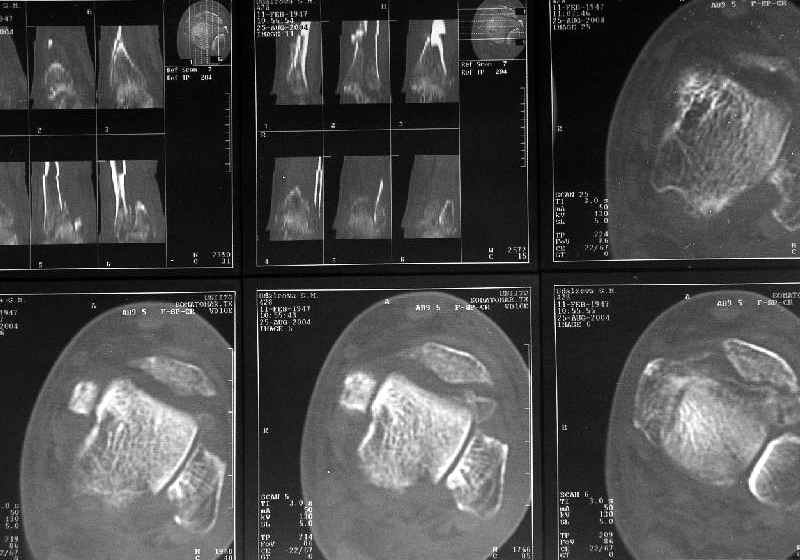

Дистальный отдел tibia - 6 недель

Дама 56 лет 6 недель назад получила спиральные переломы дистальных отделов костей голени. По месту жительства наложили гипс.

Сейчас вот, получается, спохватились. Снимки и КТ в приложении. Какой вариант тут предпочтительнее - открытая мобилизация, репозиция и внутренняя или наружная фиксация? Или ограничиться только резекцией костного шипа над шейкой тарана? Заранее спасибо. A female 56 y.o. 6 weeks ago sustained a fracture of the distal tibia/fibula. At the initial hospital a plaster cast was applied. Now she was referred to our unit. At the moment there is no pain, no obvious mobility. Images and CT attached. What is the best option here? Mobilize the fracture, perform open reduction and internal or external fixation? Or just to cut the anterior spike over the talar neck? THX in advance.